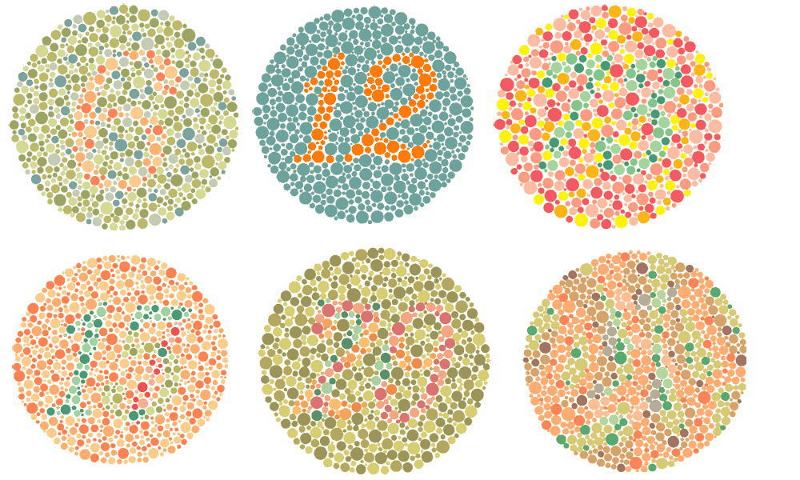

小学校時代などにやりましたね。

最近は健康診断でも時々やったりするのでしょうか。

改めて診てみましょう

この絵をみて数字は見えますか?

【解説】

答えはコメント欄で

| 【下段左】 17に見える人は 青系の色覚異常 (非常に珍しい) | 【下段中央】 70に見える人は 赤系の色覚異常 (比較的多く1.25%) | 【下段右】 5に見える人は 緑系の色覚異常 (非常に多く3.75%) |